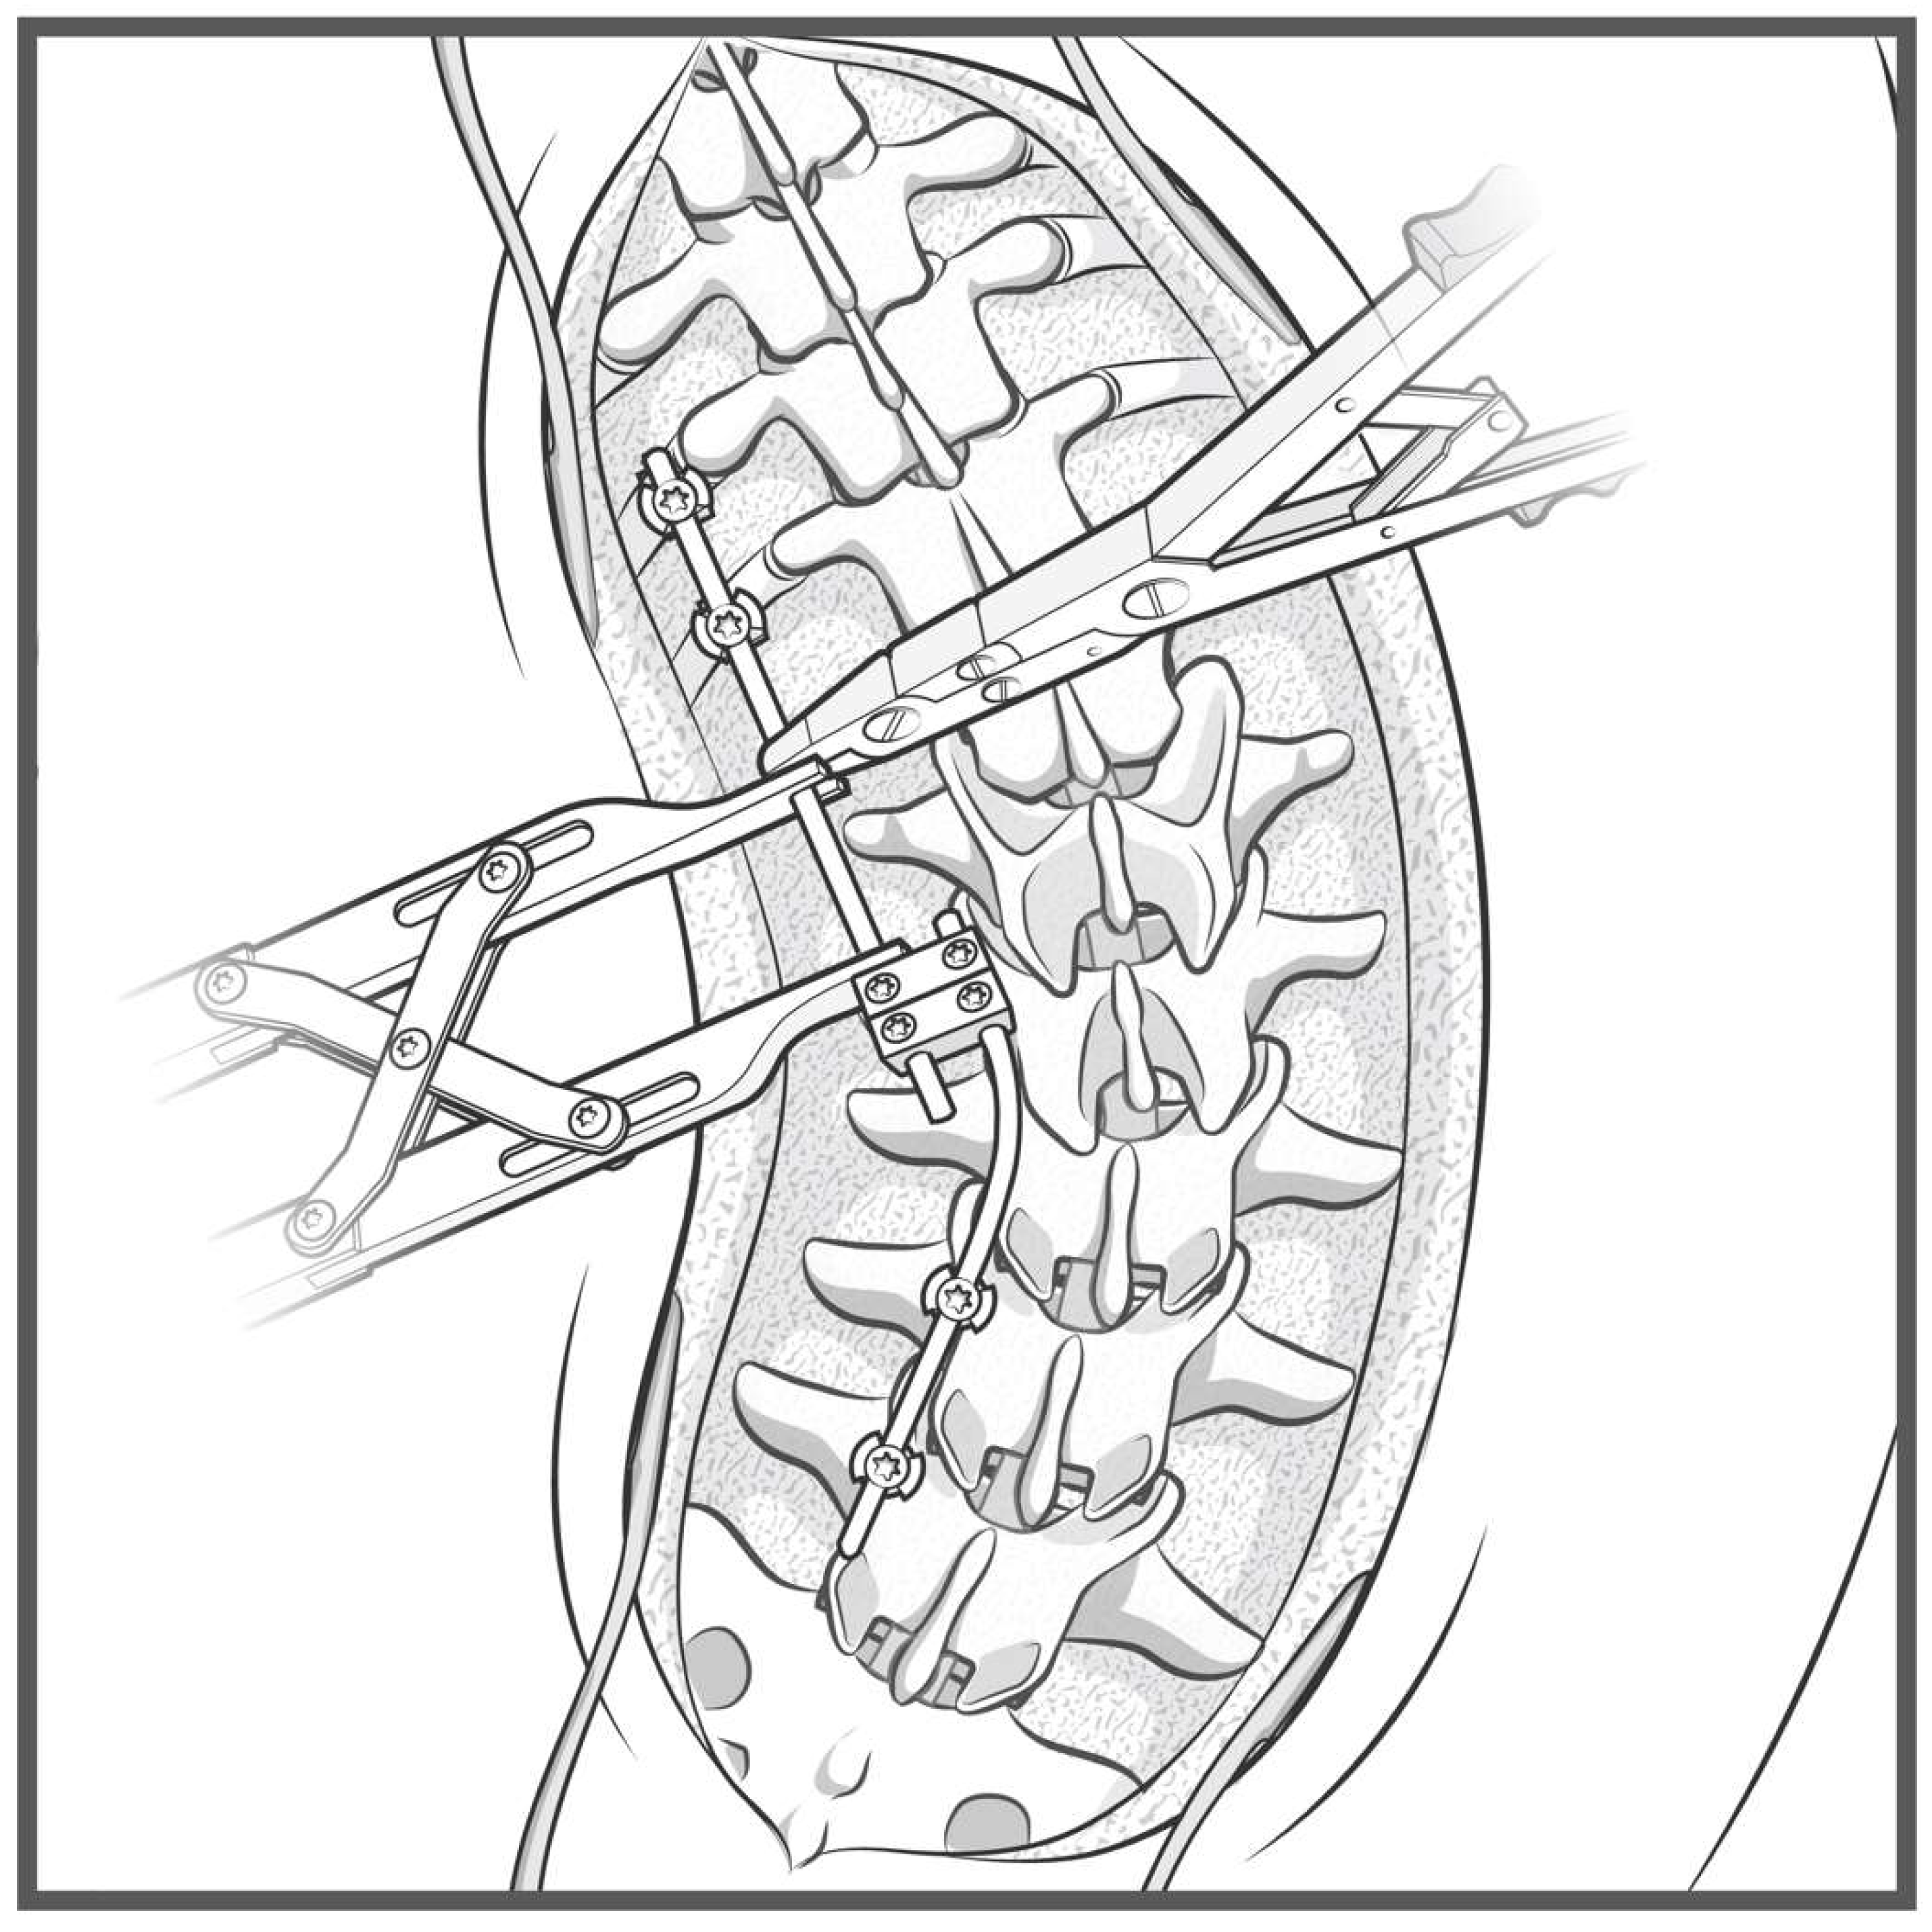

Figure 3.

Step-by-step schematic of the construct-to-construct internal distraction technique. The green caps represent loose set caps. Red caps represent tight set caps.

Figure 7.

Step-by-step schematic of the construct-to-construct internal compression technique for closure of PSO. The green caps represent loose set caps. Red caps represent tight set caps (A). Intraoperative image adapted from Bourghli et al. showing a construct-to-construct internal compression technique to close a PSO site (B).